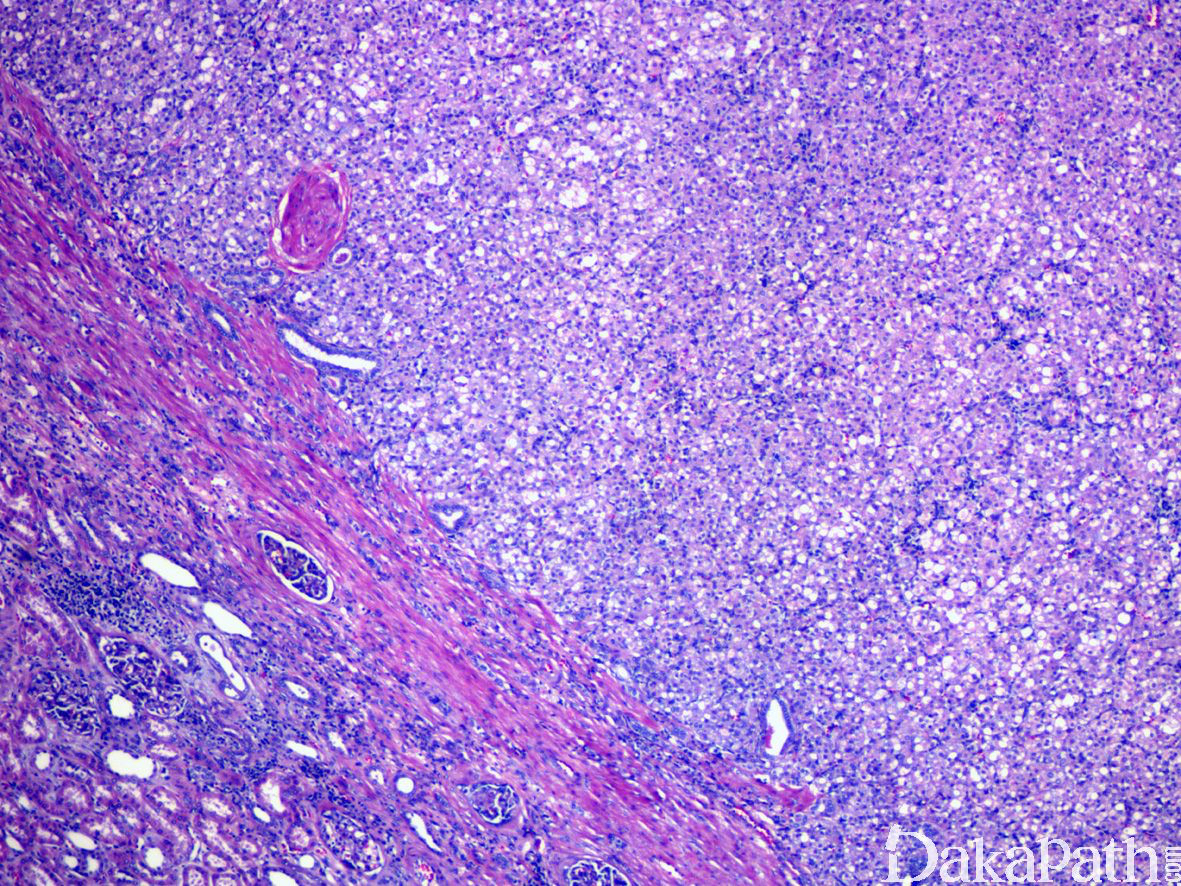

3,大体上,肿瘤通常境界清楚,切面灰红灰白,实性为主常伴有不同程度的囊性变, 30%的病例多灶或双侧发生。

4,形态学上肿瘤一般界限较清楚部分带包膜,整体上呈分叶状或推挤状状生长,周边常见内陷的良性肾小管,常表现为不规则分支和乳头状结构。瘤细胞以实性、巢状排列为主,常见不同程度的微囊或多囊性扩张以及小管形成,偶尔可见乳头状生长结构。瘤细胞胞浆丰富,嗜酸性,SDH-RCC 最具特征性的组织学表现为胞浆内存在半透明的包涵体,内含嗜酸性或浅染的絮状物质,当这一改变显著时可造成肿瘤明显的空泡状低倍观。